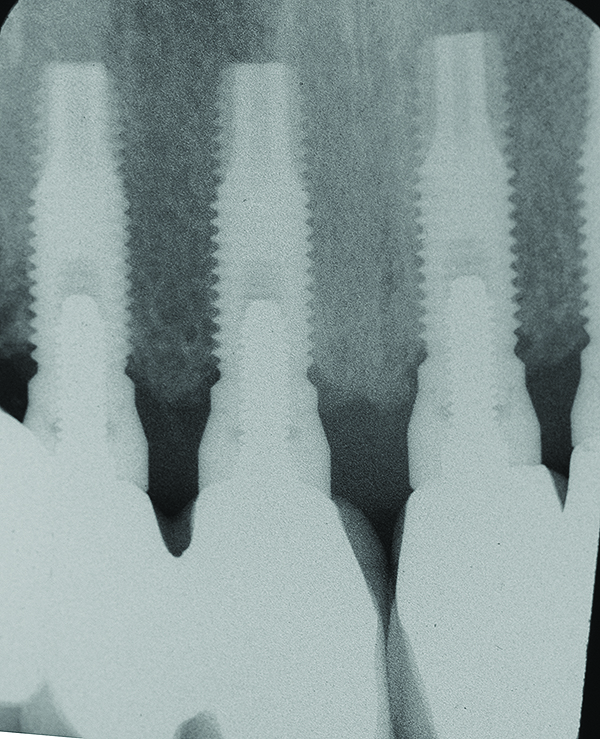

Fig 7 through Fig 14. Periapical radiographs of a 62-year-old woman who received a fixed porcelain-fused-to-metal reconstruction supported by abutments by internally connected dental implants. Fig 7 through Fig 10 are at initial prosthesis placement: mandibular site Nos. 30 and 29 (Fig 7); mandibular site Nos. 26, 25, and 23 (Fig 8); mandibular site Nos. 23 and 21 (Fig 9); mandibular site Nos. 21 through 19 (Fig 10). Fig 11 through Fig 14 are 11 years later (2013) and show excellent preservation of the vertical bone levels around the implants: mandibular site Nos. 30 and 29 (Fig 11); mandibular site Nos. 26 and 25 (Fig 12); mandibular site Nos. 25 and 23 (Fig 13); mandibular site Nos. 20 and 19 (Fig 14). It is interesting to note that in the mandibular right posterior quadrant there is a matched pair, ie, an external hex dental implant (No. 30) adjacent to an internally connected dental implant (No. 29). The bone levels around each of these designs are well-preserved at the 11-year follow-up.